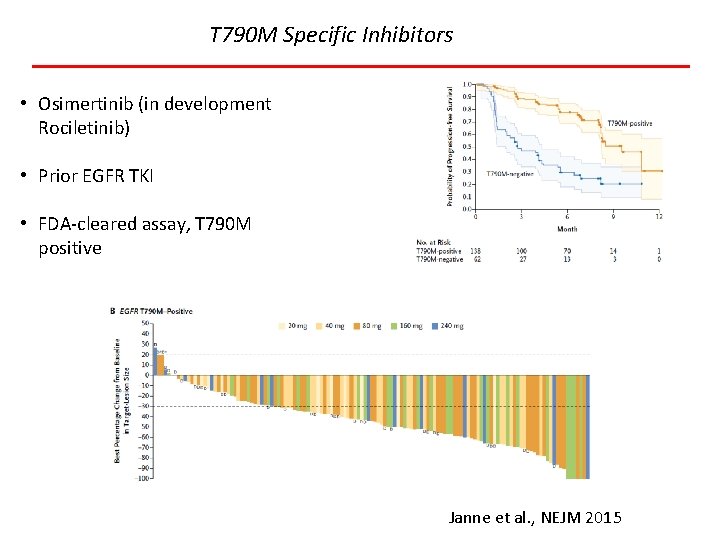

T 790 M Specific Inhibitors • Osimertinib (in development Rociletinib) • Prior EGFR TKI • FDA-cleared assay, T 790 M positive Janne et al. , NEJM 2015